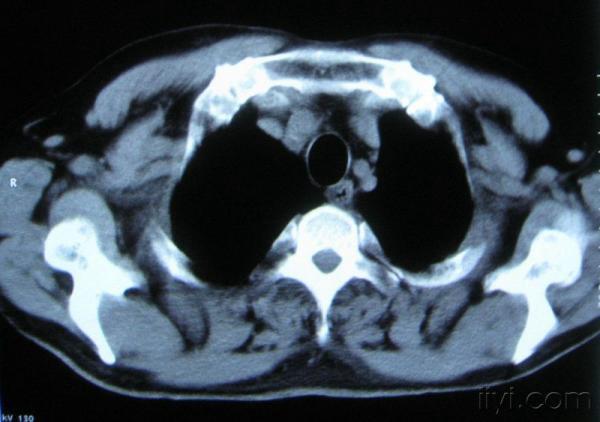

男。60岁,胸片示支气管炎治疗后复查CT。

你指那个肯定是淋巴结,中央系坏死,这很常见,特别在双侧腹股沟会经常看到。这个双侧腋窝及纵隔见多发小淋巴结征。

根据位置考虑应该是淋巴结,密度不均,是因为肿大的淋巴结中心液化坏死